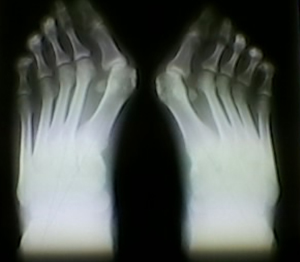

«Продольно-поперечное плоскостопие, вальгусное отклонение первых пальцев, молот-кообразные деформации 2, 3, 4 пальцев, метатарзалгия обеих стоп» (рис. 2, 3). Были произведены следующие реконструктивные операции на передних отделах стоп: остеотомии SCARF первых плюсневых костей, остеотомии Weil 2, 3, 4, 5 плюсневых костей. Уже в раннем послеоперационном периоде был отмечен неудовлетворительный результат: вальгусное отклонение первых пальцев сохранялось, также имело место вальгусное отклонение 2, 3, 4 плюсневых костей. Через 3 месяца появилась боль под головками 3, 4 плюсневых костей. В течение года боли под головками 3,4 продолжали нарастать.

Пациентка была повторно госпитализирована. После выполнения ревизионной операции (Артродез медиальных плюснеклиновидных суставов, проксимальная остеотомия 2,3, 4 плюсневых костей) клинически и рентгенологически коррекция была достигнута. Через 3 месяца после операции пациентка была довольна результатом, косметический дефект устранен, боли отсутствуют (рис. 4, 5).